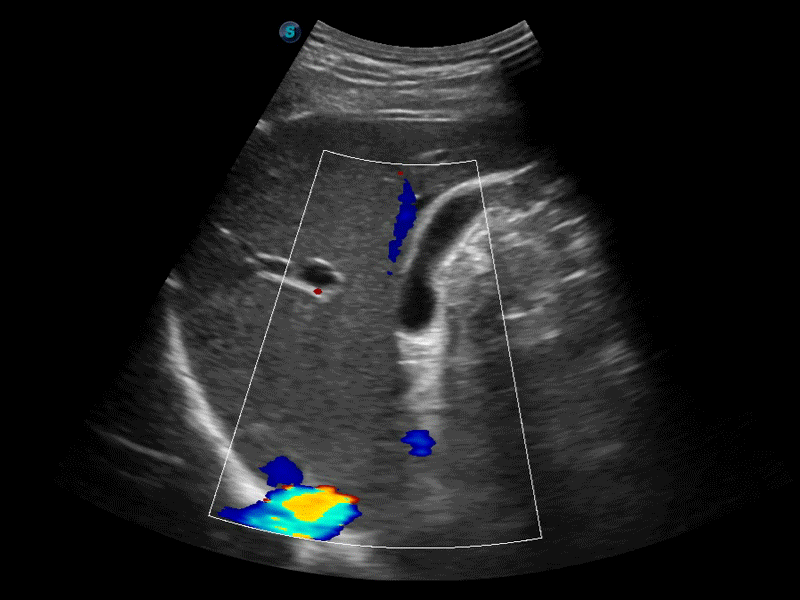

高分辨率血流成像技术提高了对低速血流信号的检测能力。在提高空间分辨率的同时,也克服了血流外溢现象,为用户提供更加真实的血流动力学信息。

凸阵、线阵和相控阵探头进行实时扫描时,开启扩展成像模式,可以扩展超声图像视野,以便更完整地查看大的病灶或组织器官的解剖结构。